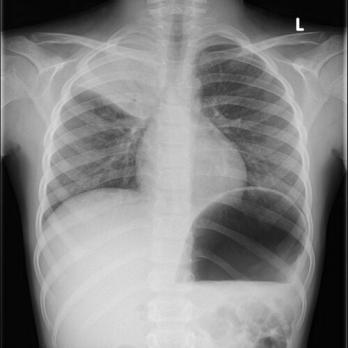

CRP en BSE Lees meer over CRP en BSE CRP en BSE

De laboratoriumbepalingen bezinking (bezinkingssnelheid erytrocyten, BSE), het C-reactieve proteïne (CRP) en de leukocyten worden in de kliniek veelvuldig aangevraagd ter analyse van een onderliggende ziekte of worden serieel gemeten bij het vervolgen van een ziekte. Hoe deze bepalingen geïnterpreteerd dienen te worden, wordt geïllustreerd aan de hand van een casus.